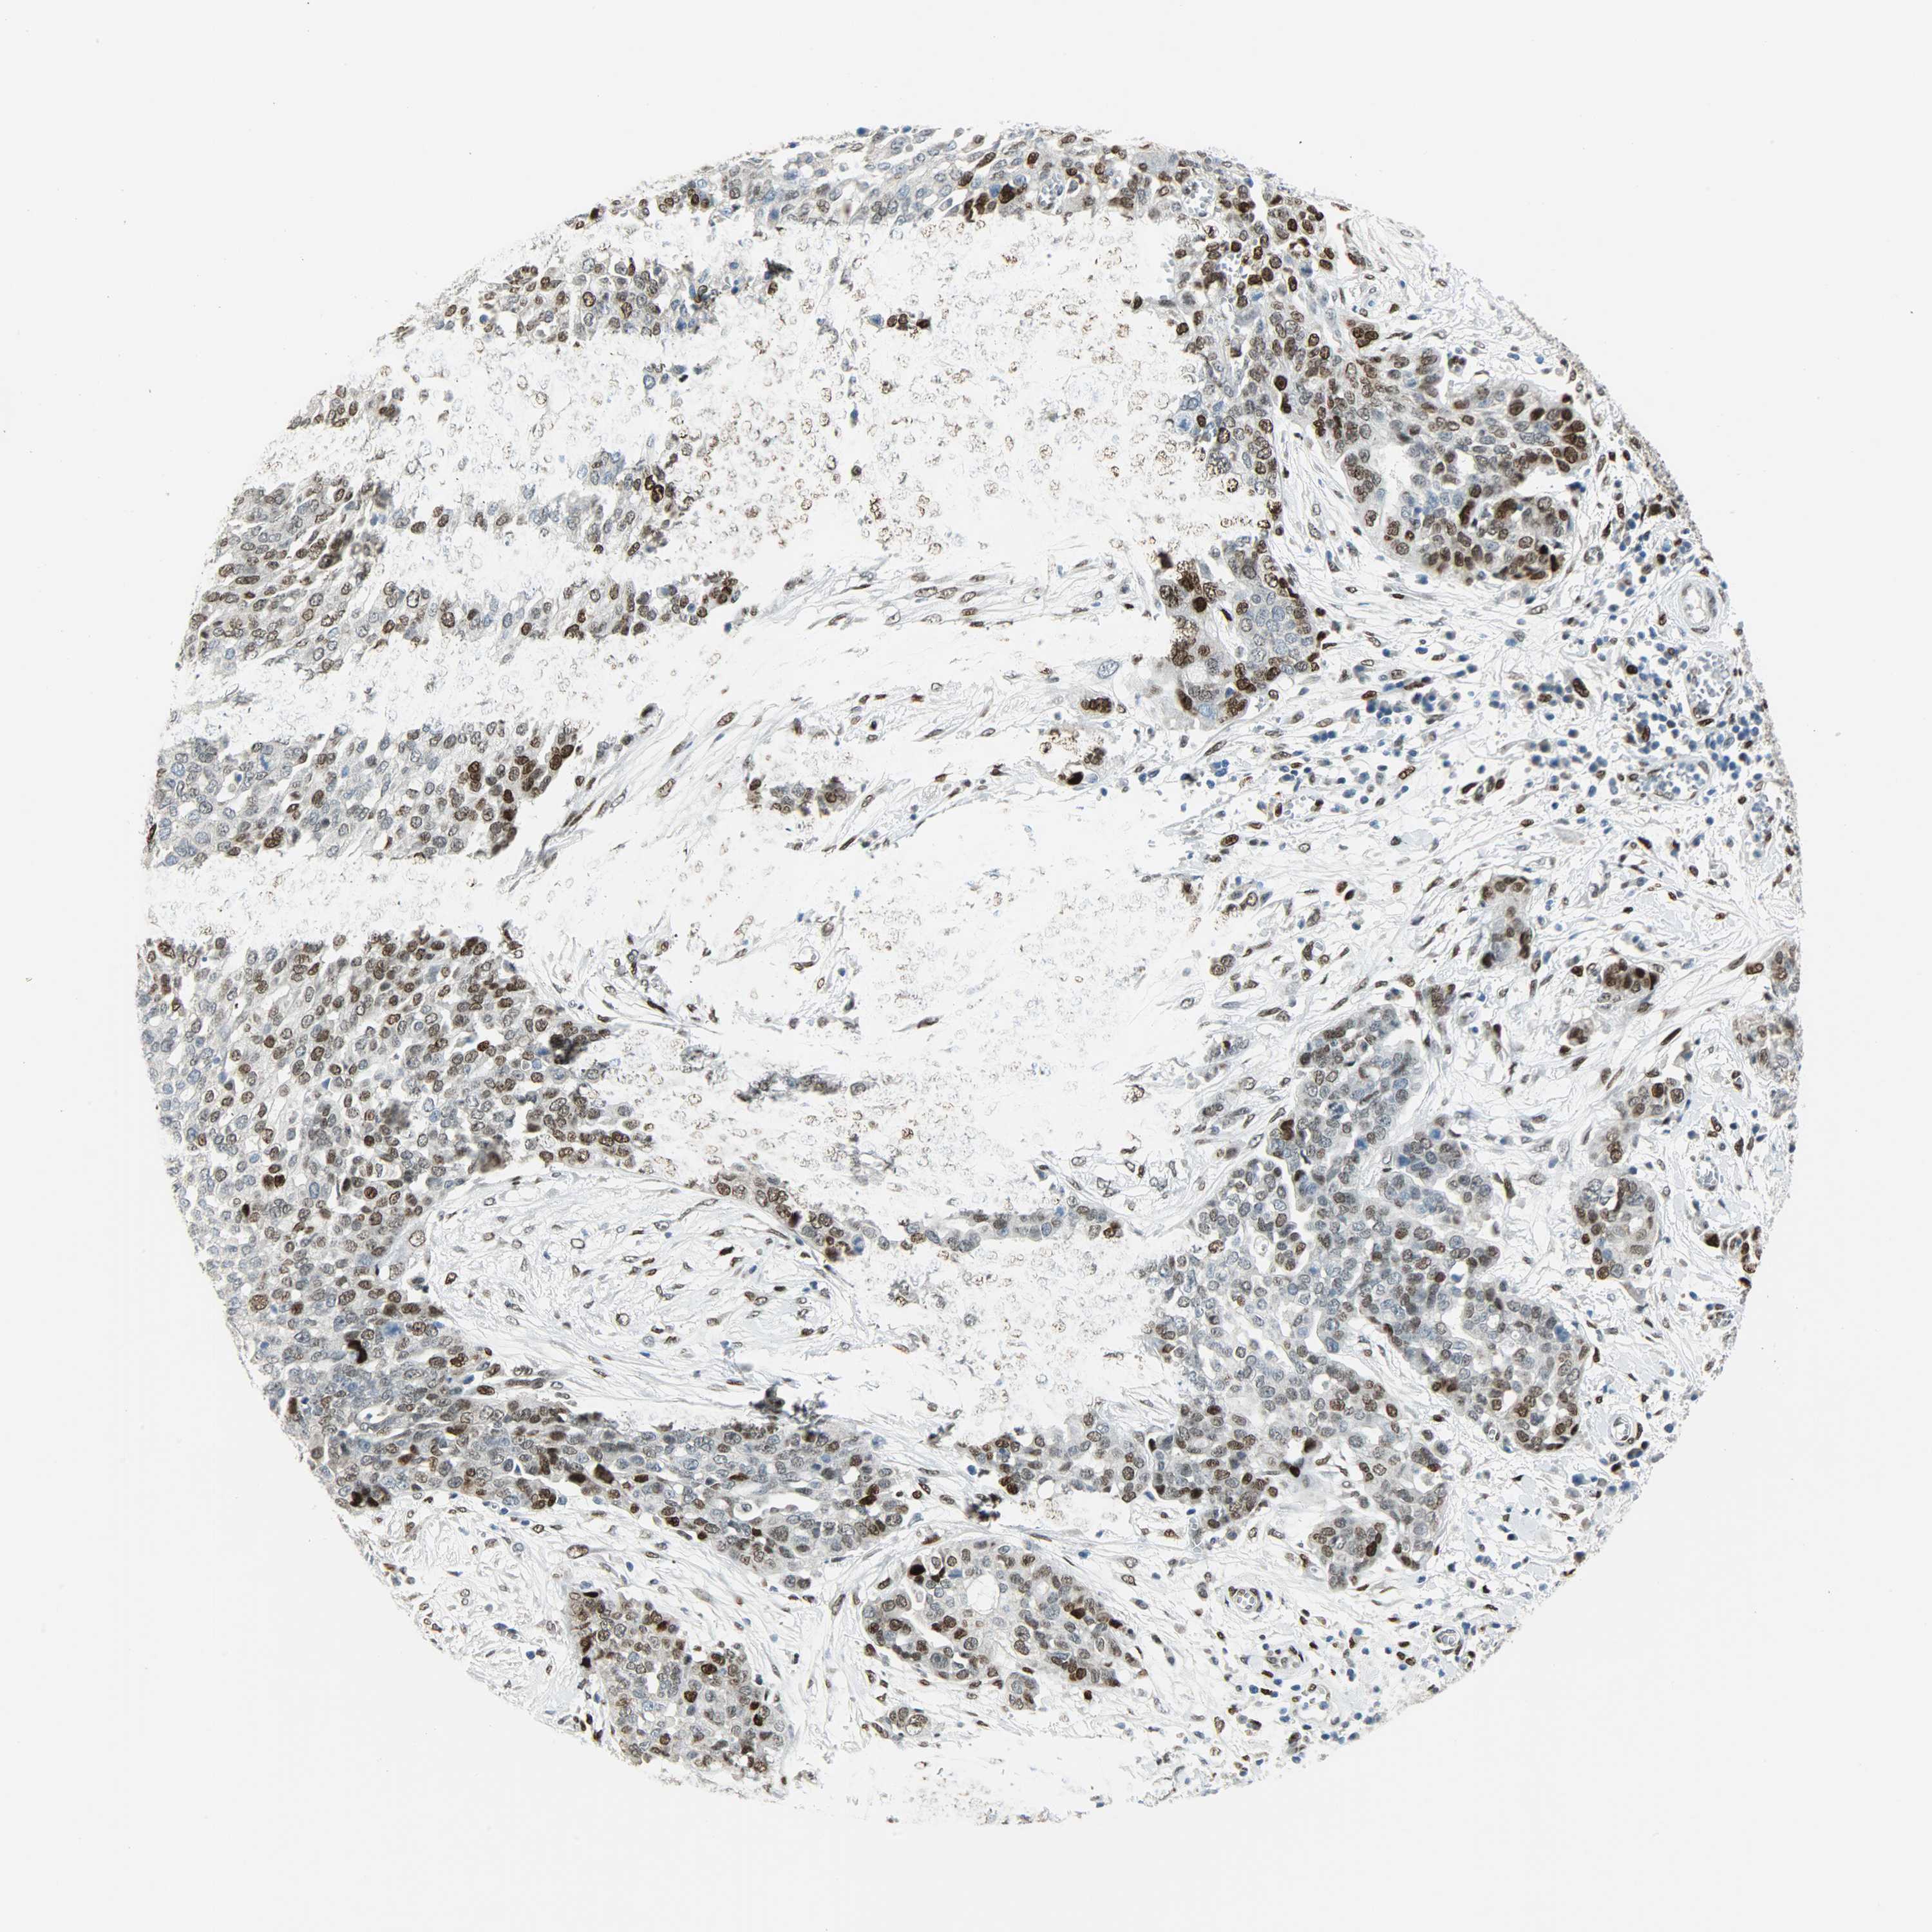

OVARIAN CANCER - Protein expressioni

A mouse-over function shows sample information and annotation data. Click on an image to view it in a full screen mode. Samples can be filtered based on level of antibody staining by selecting one or several of the following categories: high, medium, low and not detected. The assay and annotation is described here.

Note that samples used for immunohistochemistry by the Human Protein Atlas do not correspond to samples in the TCGA dataset.

Antibody stainingi

Antibody staining in the annotated cell types in the current human tissue is reported as not detected, low, medium, or high, based on conventional immunohistochemistry profiling in selected tissues. This score is based on the combination of the staining intensity and fraction of stained cells.

Each image is clickable and will lead to virtual microscopy that enables deeper exploration of all samples and also displays staining intensity scores, fraction scores and subcellular localization as well as patient and tissue information for each sample.

Antibody HPA019149

Antibody CAB004464

Staining

High

Medium

Low

Not detected

Intensity

Strong

Moderate

Weak

Negative

Quantity

>75%

75%-25%

<25%

None

Location

Nuclear

Cytoplasmic/membranous

Cytoplasmic/membranous,nuclear

Cystadenocarcinoma, serous, NOS

Carcinoma, endometroid

Cystadenocarcinoma, mucinous, NOS

Carcinoma, NOS